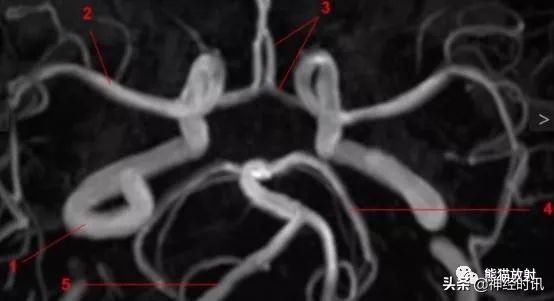

MRA解剖圖:(MIP TOF序列)

1、頸內動脈;2、大腦中動脈;3、大腦前動脈;4、大腦後動脈;5、椎動脈。